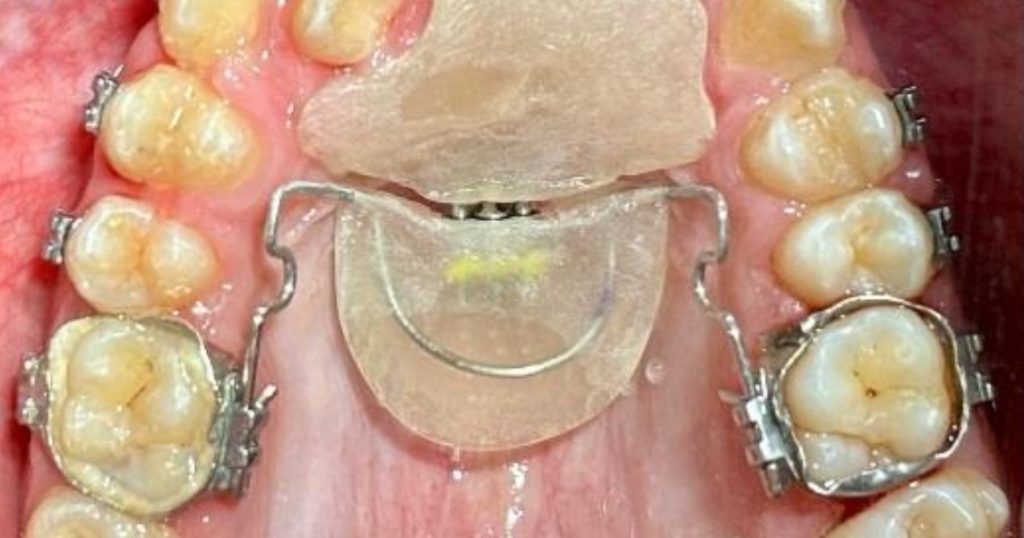

Los autores destacan que las discrepancias transversales pueden generar alteraciones funcionales y estéticas si no se tratan oportunamente. La expansión maxilar busca corregir estas deficiencias mediante la disyunción de la sutura palatina media y la remodelación ósea, siendo su eficacia dependiente de la edad y del tipo de dispositivo empleado.